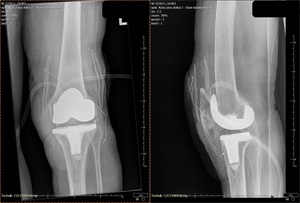

The patient was admitted again to our clinic on the 12th of September for TKA. The patient signed a separate informed consent for this procedure. An anterior approach was used. A cemented implant with an antibiotic was used. The patient was able to walk using walking aids on the 3rd day following TKA. The time to perform the procedure was 1,2h. The blood count parameters – RGB and HGB were only slightly below normal limits after surgery (3,0 M/ul, 9,4 g/dL), and electrolyte status was within normal limits. Anticoagulants were resumed 12h post-surgery, as during the previous hospitalization. Hemodialysis was scheduled every 3rd day during the hospitalization period. The patient was discharged on the 18th of September and instructed to walk without weight-bearing on the left lower limb until the follow-up visit, which was scheduled for the 2nd of October.

At the latest follow-up visit on the 29th of December, 2019 patient presented pain-free. His range of movement has dramatically increased. Hip joint’s range of motion – flexion 110°, extension – 10°. external and internal rotation – both 35°. Knee joint – flexion 110°, with no flexure contracture present. The patient was asked to evaluate his [quality of life (QoL)] using a [visual analog scale (VAS)] – in increased from 30/100 (measured preoperatively) to 85/100 after both procedures. He was generally satisfied with the results and declared he can drive a car without limitations and walk longer distances (above 1km).